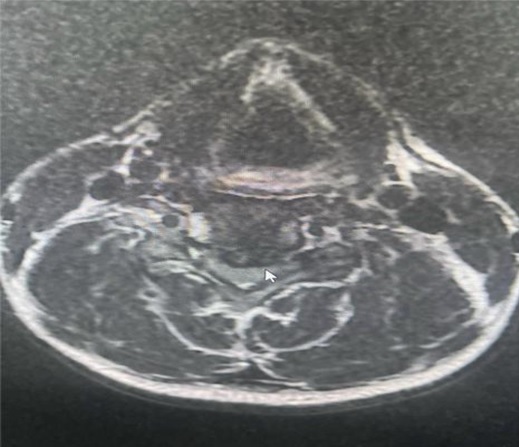

Hình ảnh MRI thoát vị đĩa đệm C4-C5 chèn ép tủy sống trước mổ

Qua thăm khám, các bác sĩ khoa Phẫu thuật Thần kinh Lồng ngực ghi nhận cơ lực hai tay giảm còn 4/5, kèm theo dấu hiệu chèn ép rễ thần kinh cổ. Hình ảnh cộng hưởng từ (MRI) cột sống cổ cho thấy khối thoát vị đĩa đệm cột sống cổ tầng C4–C5, khối thoát vị gây chèn ép thần kinh, phù hợp với biểu hiện lâm sàng của người bệnh.